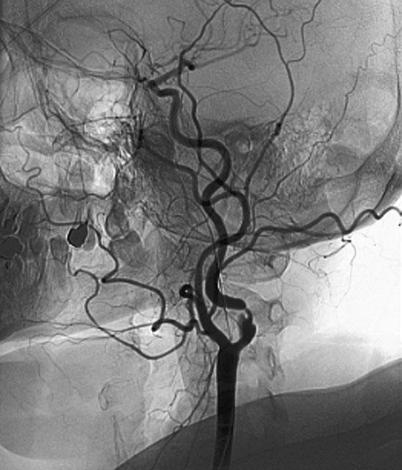

Мы стоим у мертвого дерева и пытаемся понять, почему оно погибло. Ответ в общем-то прост: в его структуре нарушилась система циркуляции для подачи питательных веществ. Что-то похожее происходит и с человеком, когда в его организме нарушается система циркуляции крови. При закупорке артерий сердца развивается инфаркт, артерий головы – инсульт, при серьезных проблемах в артериях ног вероятна гангрена.

Болезни системы кровообращения и вызванные ими осложнения занимают первую строчку в списке смертности россиян и уступать свои позиции не намерены. В стране ежегодно регистрируется около 500 тысяч инсультов и примерно 450 тысяч инфарктов, причем эти цифры постоянно растут. Впрочем, это мировая тенденция, хотя медицина не стоит на месте. «Исследования, проведенные в США и ряде европейских стран, показали, что надежды, возлагаемые на высокотехнологические виды помощи как средства первой линии для борьбы с сердечно-сосудистыми заболеваниями, не оправдались, – отмечает академик РАМН Рафаэль Оганов. – Несмотря на огромное количество баллонных ангиопластик и операций аортокоронарного шунтирования, выполняемых в экономически развитых странах (1,6 миллиона вмешательств ежегодно только в США), остановить эпидемию сердечно-сосудистых заболеваний и изменить их ведущий вклад в структуру смертности не удалось».

Векторы сил артериального и венозного кровотока каждого сегмента тела направлены в противоположных направлениях. Величины векторов сил артериального кровотока уменьшаются от сердца к периферии, а величины векторов сил венозного кровотока, наоборот, увеличиваются от периферии к сердцу. Не вдаваясь в тонкости, отметим главное: при воздействии на этот процесс магнитными силами может изменяться не только физико-химическое состояние крови, но и состояние стенок сосудов.

Это теоретическая основа, на которой Епифанов разработал свой метод. Его скафандры – если уж совсем упростить – разгоняют кровь по сосудам в нужном направлении и с нужной скоростью.

Таким образом, по Епифанову, происходит возвращение энергетических констант к нормальному уровню, что приводит к исчезновению у человека отрицательных ощущений и затуханию негативных реакций со стороны иммунной системы. Главный эффект – в нормализации энергетического гомеостаза и связанных с ним свойств крови. Например, у больных атеросклерозом лечебный эффект проявляется за счет увеличения теплопродукции в конечностях, а у больных с эндартериитом – за счет уменьшения сосудистого тонуса.